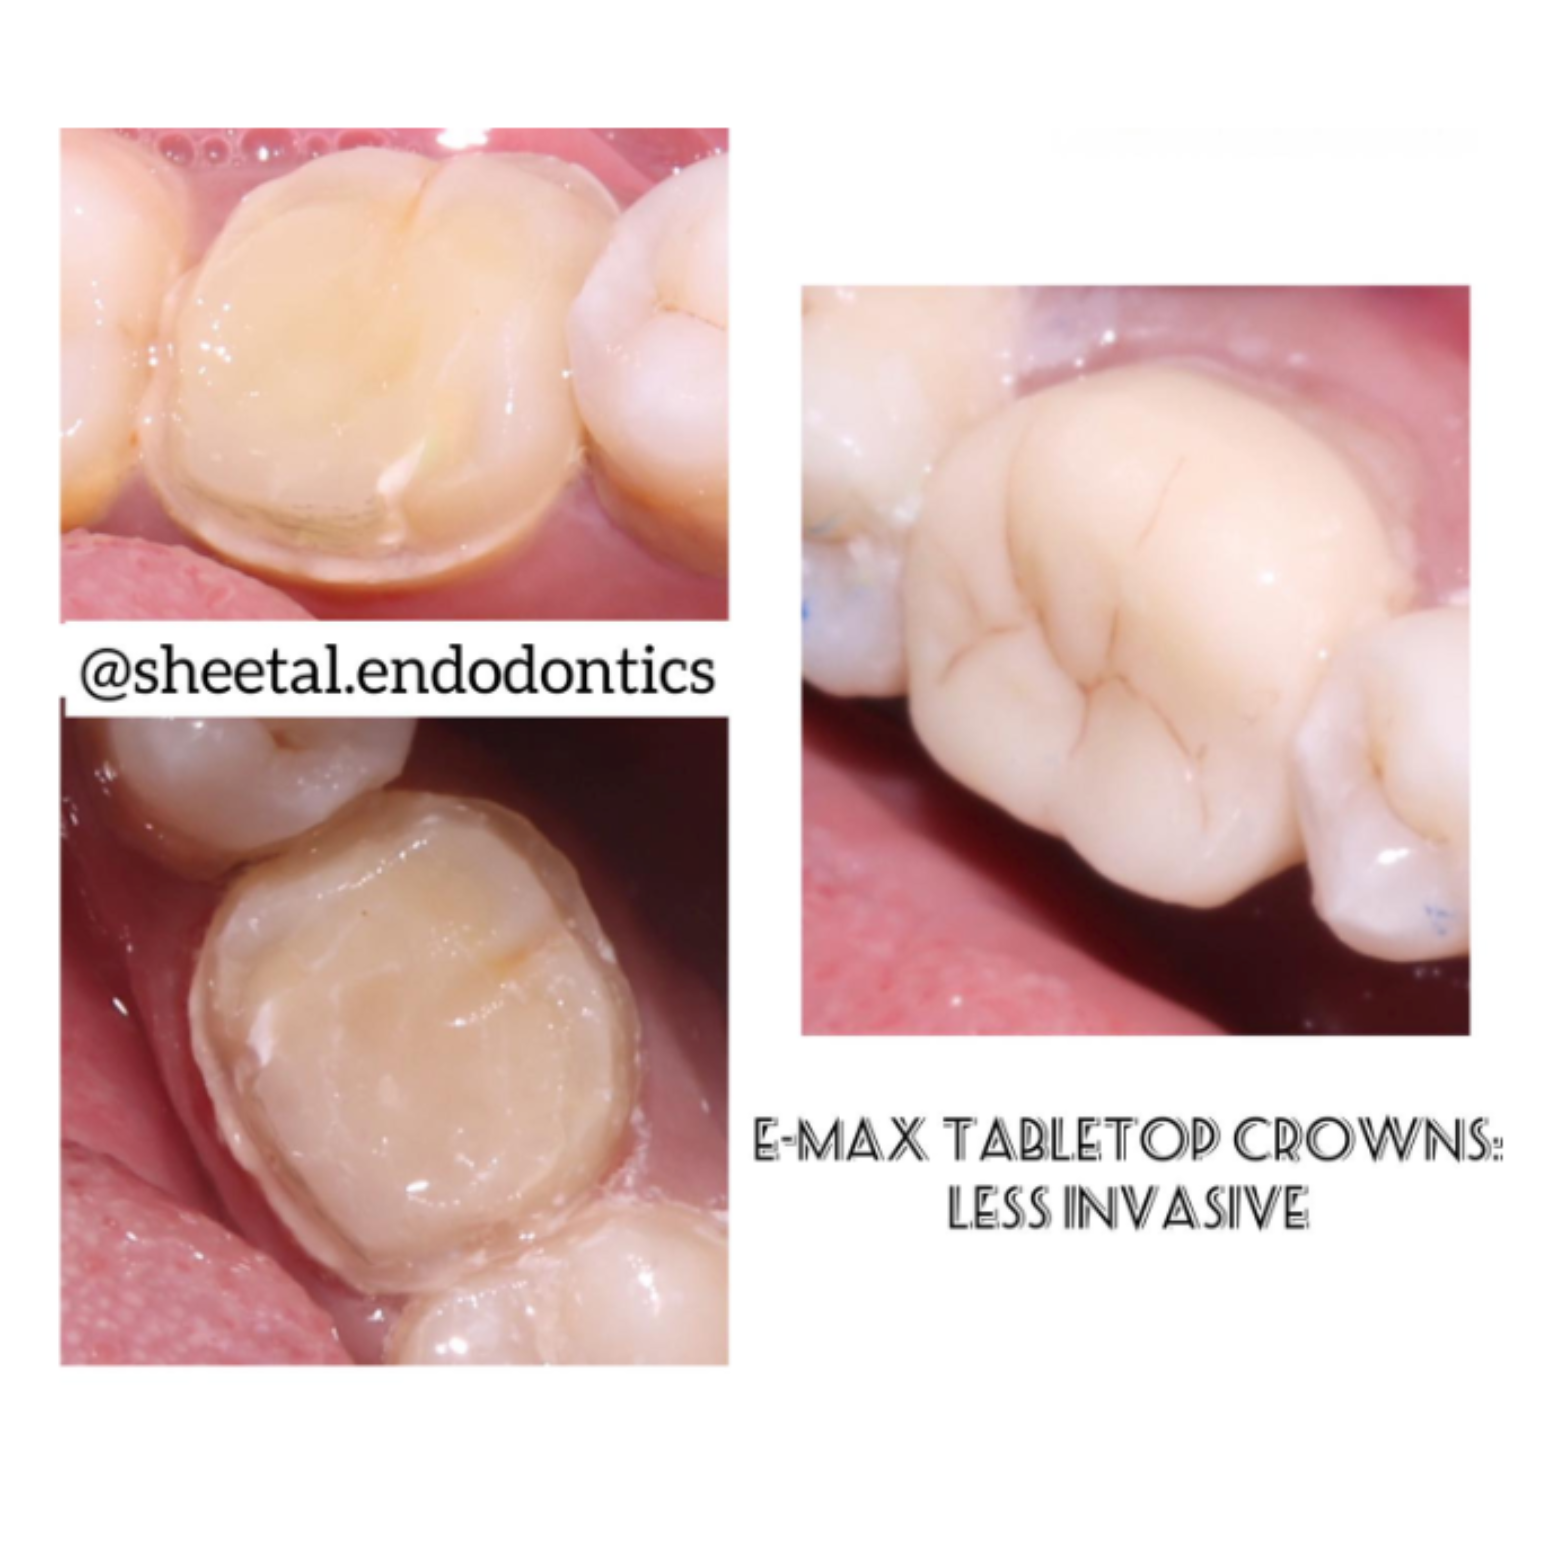

Crowns & Bridges

We utilize advanced digital impression technology to craft crowns and bridges with exceptional accuracy.